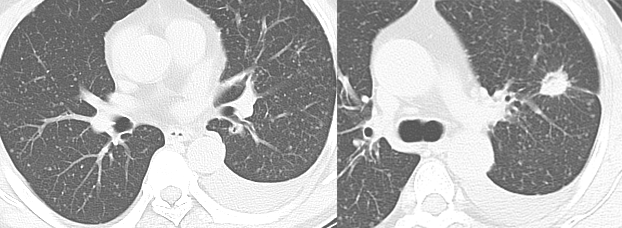

乳腺癌空洞性肺转移。

图片

54 岁男性,肾癌病史。左肺下叶厚壁空洞性转移(穿刺证实),左肺另见不伴空洞的实性小结节转移灶。

男,63 岁。食管鳞癌术后 3 年,痰中带血丝半年。穿刺证实双肺多发空洞和空泡转移,周围磨玻璃密度是转移瘤引起出血。